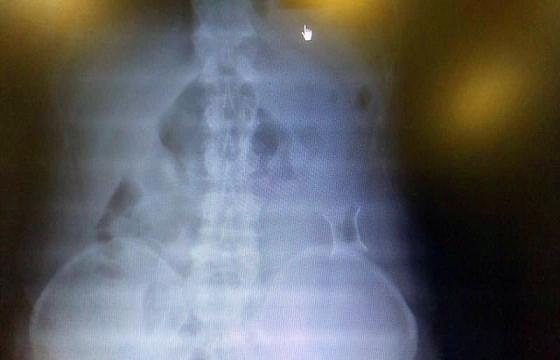

受試患者在結(jié)腸端端吻合術(shù)中,使用我司新研制產(chǎn)品達(dá)到了理想的預(yù)期效果。患者術(shù)后7天、14天X光片顯影,可降解腸道支架均能按研制設(shè)計的預(yù)期時間節(jié)點保持應(yīng)有強(qiáng)度,術(shù)后21天X光片顯示可降解腸道支架已完全破碎,并排出體外。在整個試驗過程中,病患無任何不良反映,耐受良好。